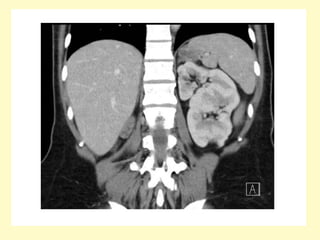

4-Prune Belly Syndrome :

-Rare anomaly comprising a specific constellation of

features

-It consists of three major findings :

1-Gross ureteric dilatation

2-Anterior abdominal wall underdevelopment (resulting in

the prune belly appearance)

3-Bilateral undescended testes (cryptorchidism) in males

-There is often an association with other respiratory,

gastrointestinal, musculoskeletal, and cardiovascular

anomalies

-It is also known as Eagle Barrett syndrome or triad

syndrome

-Urinary tract abnormalities include :

1-Bilateral hydroureteronephrosis: often with

extremely dilated, tortuous ureters

2-Varying degrees of renal dysplasia

3-Enlarged urinary bladder, often with urachal

diverticulum

4-Vesicoureteral reflux is common

5-Poor bladder contractility

6-Dilated posterior urethra without urethral

obstruction